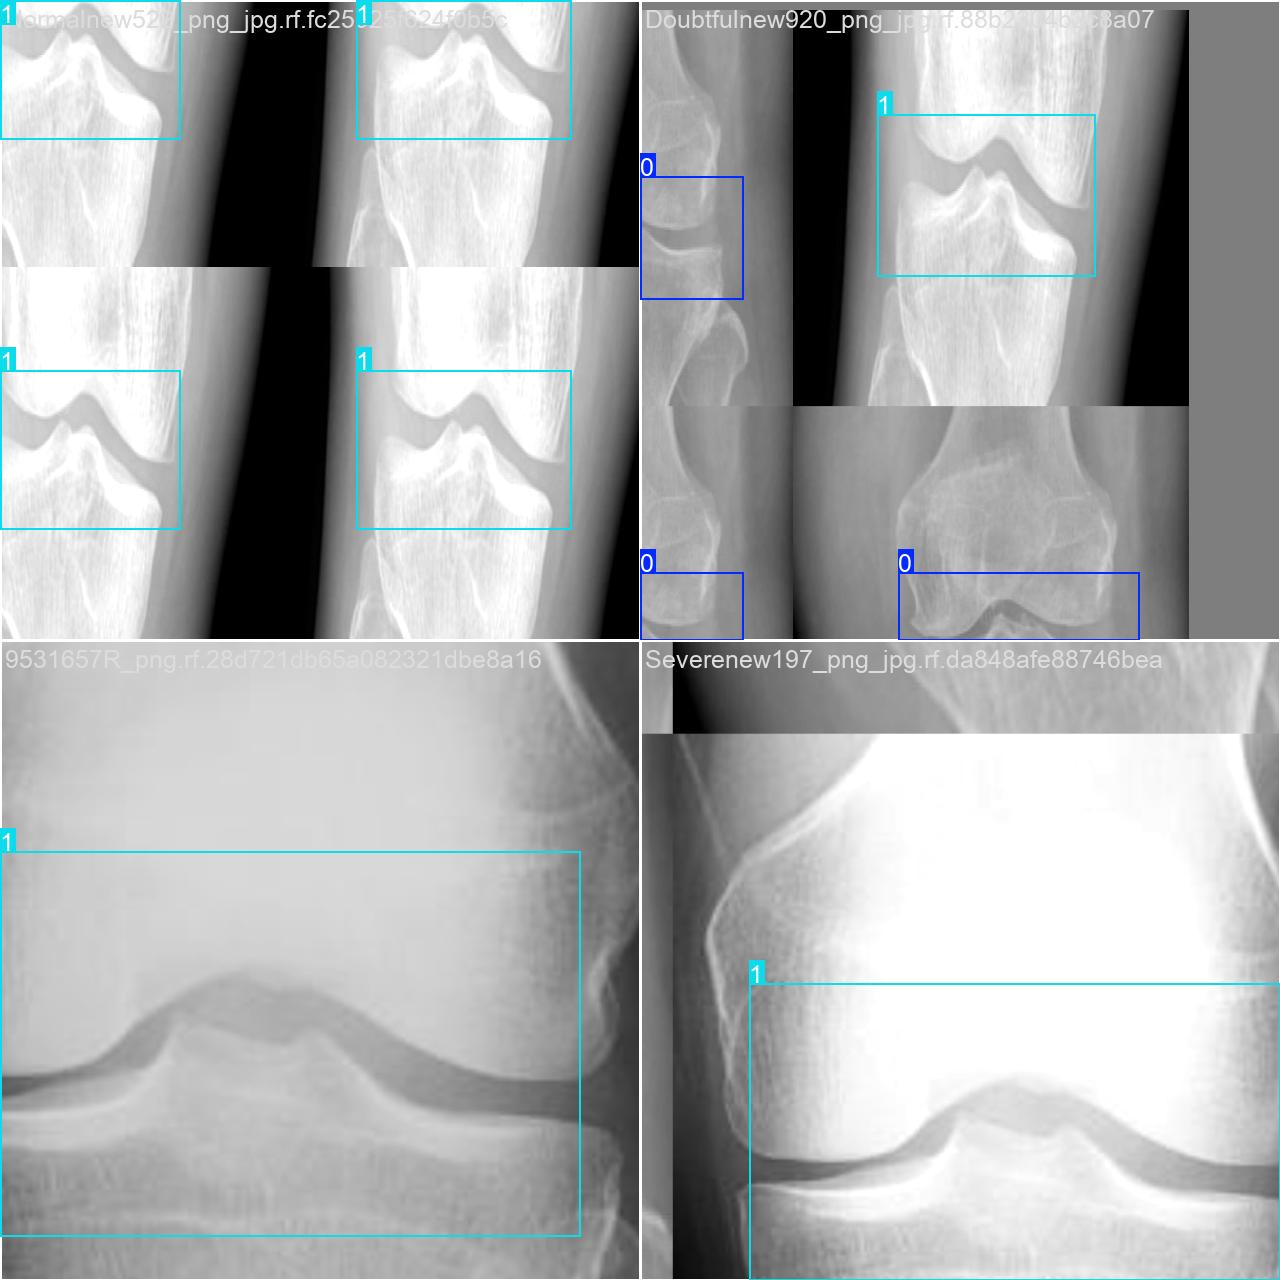

部分数据集图像如下图所示:

部分标注如下图所示:

这种数据分布方式保证了数据在模型训练、验证和测试阶段的均衡性,为 YOLOv8n 模型的开发与性能评估奠定了坚实基础。